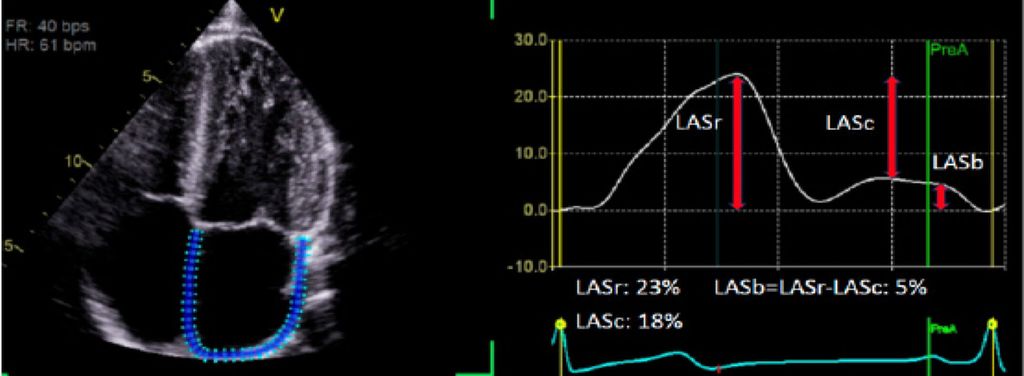

Die Analyse des „left atrial strain“ (LA Strain) basiert auf der „speckle-tracking“ Echokardiografie. Dabei werden standardisierte Echoaufnahmen des linken Vorhofs softwaregestützt ausgewertet. Die Methode verfolgt die Deformationsbewegung des Vorhofmyokards über den Herzzyklus hinweg. Aus dieser Bewegung werden prozentuale Längenänderungen („strain“) berechnet. Entscheidend ist, dass der „LA strain“ nicht nur die Größe des linken Vorhofs abbildet (wie etwa das linksatriale Volumen), sondern dessen funktionelle Leistungsfähigkeit. Drei Phasen werden üblicherweise unterschieden (Abb. 1):

Abb. 1: Abbildung eines LA Strain mit eingezeichnetem Strain. Abkürzungen: LASr = „Left atrial reservoir strain“ LASc = „Left atrial conduit strain“ LASb = „Left atrial booster strain“

„Reservoir strain“

Beschreibt die Fähigkeit des linken Vorhofs, sich während der Ventrikelsystole zu dehnen und Blut aus den Pulmonalvenen aufzunehmen. Eine eingeschränkte Reservoirfunktion spricht für verminderte Compliance und strukturelle Umbauvorgänge (Fibrose).

„Conduit strain“

Entspricht der passiven Weiterleitung des Bluts aus dem linken Vorhof in den linken Ventrikel in der frühen Diastole. Diese Phase reflektiert die Interaktion zwischen Vorhof und Ventrikel.

„Contraction strain“

Erfasst die aktive Kontraktion des linken Vorhofs in der späten Diastole („atrial kick“). Dieser Beitrag ist bei HCM-Patient:innen hämodynamisch bedeutsam. Eine eingeschränkte kontraktive Vorhoffunktion ist klinisch brisant, da genau dieser Mechanismus beim Auftreten von Vorhofflimmern wegfällt.